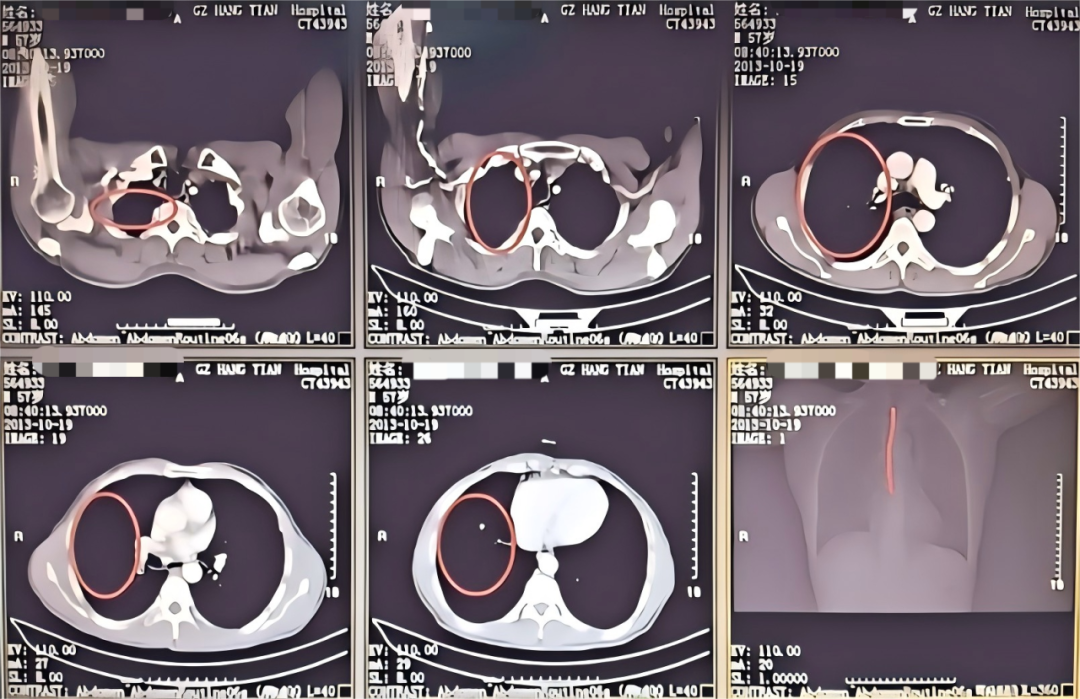

患者潘某某,因咯血在某县医院治疗效果不佳转入我院呼吸与危重症医学科,转入后出现大咯血2次,咯血量近2000ml,患者一度面临生命危险,在科室的充分讨论评估后,决定为患者进行支气管动脉栓塞术止血。

术 前

术 后

在实施支气管动脉栓塞术止血后,考虑到患者大量咯血后血液会阻塞气道,科室团队当即进行CT扫描,发现右肺已被凝血块完全阻塞,立即在床边通过气管镜清理气道内凝血块。术后,患者再无咯血,经住院治疗一段时间后,患者复查CT右肺基本恢复,顺利出院。